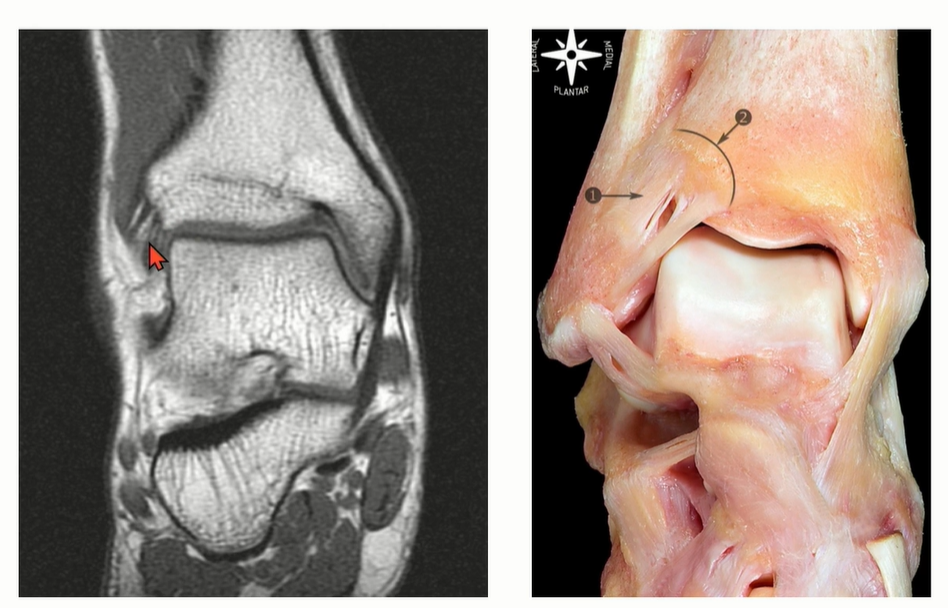

2-2 . CFL (Calcaneofibular ligament)

ATFL과 떨어져서 기시한다는 이야기도 있었지만, Just below ATFL로 이해하면 좋을 것 같다.

Peroneal tendon을 landmark로 이용해서 CFL를 찾는 것도 연습해야 함.

Axial cut과 coronal cut에서 모두 확인할 수 있는데, Axial cut의 경우에는 peroneal tendon 내부에 위치한 것을 확인할 수 있다.